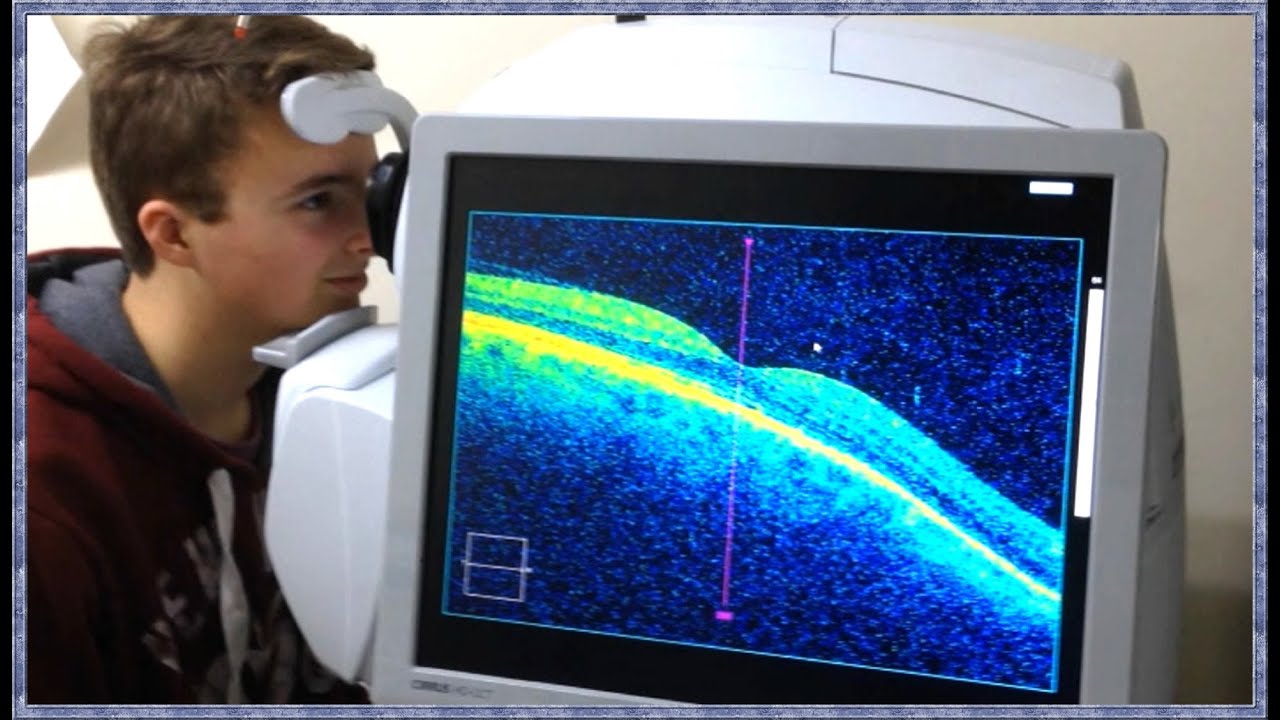

Диагностика зрения: Когерентная томография сетчатки